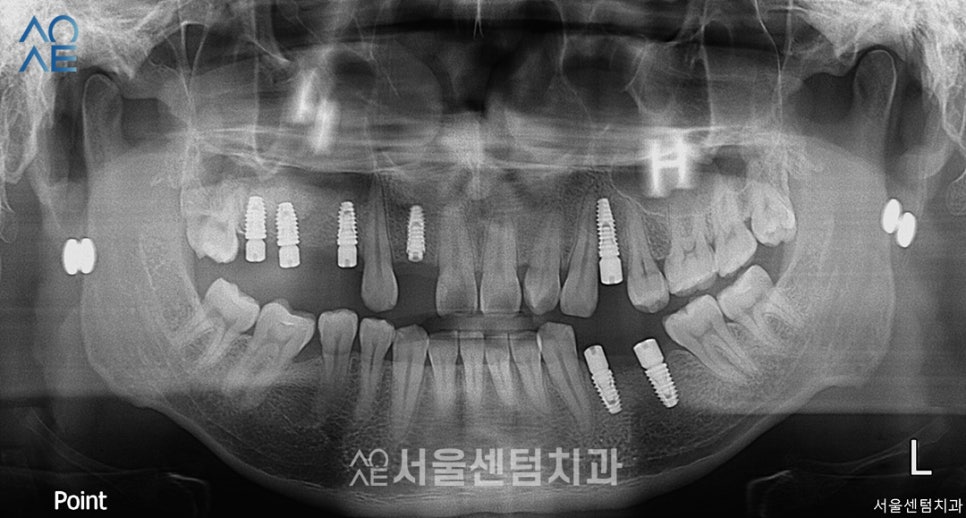

어금니는 이미 상실한 상태였고

다른 치과에서도

임플란트가 필요하다는 말을 들으셨다고 합니다.

| (1) 현재 상태🔹기존 보철물 치료를 하셨음→보철물 제거 후 엑스레이 촬영 필요🔹잇몸뼈 부족 |

| (2) 치료 계획🔹24번 치아 발치🔹위/아래 총 7개 임플란트 식립+뼈이식 필요 |

상담 당일에 바로 수술을 진행했습니다.

또 잇몸뼈가 부족하다고 진단했기 때문에

뼈이식도 함께 진행했습니다.

이날은 2개만 먼저 진행했으며

충분히 잇몸뼈가 형성되는 기간이 필요하기에

5주 뒤 ct촬영 후 2차수술을 진행하기로 했습니다.